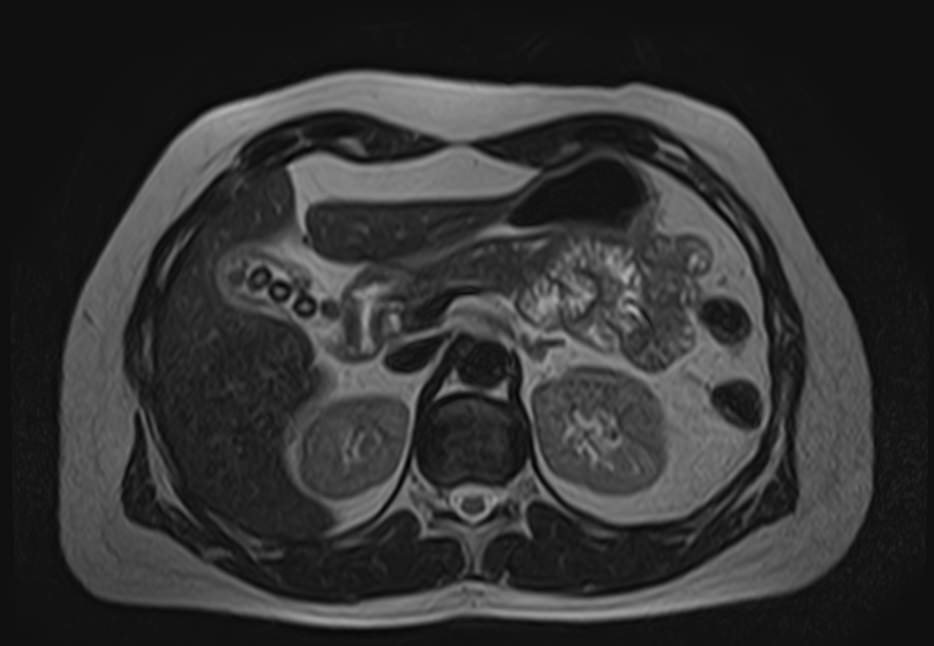

В процессе МРТ поджелудочной железы получают серию снимков органа, по которым можно оценить следующие параметры:

- топографию железы;

- форму;

- взаимоотношение с окружающими структурами;

- четкость контуров;

- целостность капсулы;

- структуру паренхимы;

- проходимость протоков.

МР-томография выступает уточняющим методом диагностики при сомнительных результатах УЗИ. Процедура позволяет определить характер, локализацию и масштабы патологического процесса.

Метод применяют при подозрении на онкологический процесс для первичной дифференциации доброкачественных и злокачественных опухолей. Подробные сведения об анатомии поджелудочной железы позволяют исключить осложнения панкреатита. МРТ также применяется для подготовки к хирургическим операциям и контроля результативности лечения.